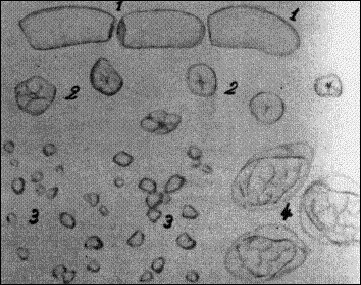

EIKONA 1.  Μικροσκοπική εικόνα κοπράνων.  1 = Κυτταρίνη μπανάνας, 2 = Άμυλο αραβοσίτου,

3 = Άμυλο ρυζιού, 4 = Υπόλειμμα φασολιού  (Κονιαβίτης 1968).

Κατά τη μικροσκοπική εξέταση παρατηρούνται υπολείμματα μυϊκών ινών και ινών συνδετικού ιστού αν υπάρχει διαταραχή της πέψης των λευκωμάτων, λιποειδείς ουσίες επί ελαττωματικής πέψης των λιπών και αμυλόκοκκοι από ανωμαλίες στην πέψη των υδατανθράκων (Εικ. 1).

ΕΙΚΟΝΑ 3.  Αμυλόκοκκοι χρωματισμένοι με Lugol.

Μεμονωμένοι αμυλόκοκκοι βρίσκονται και σε φυσιολογικά κόπρανα ιδίως των βρεφών. Μεγάλη αύξησή τους σημαίνει δυσλειτουργία του λεπτού εντέρου.  Οι αμυλόκοκκοι αναγνωρίζονται εύκολα γιατί στο χρωσμένο με Lugol παρασκεύασμα βάφονται μπλε (Εικ. 1 και Εικ. 3).